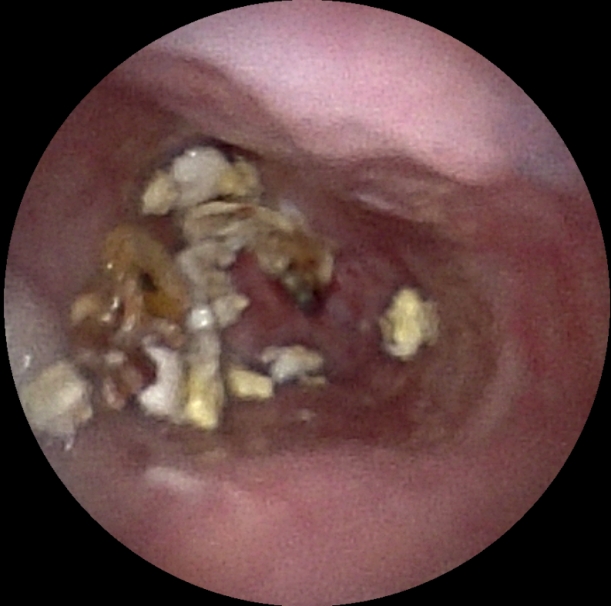

术前、术中、完成造瘘的食管

食管癌发展至中晚期,常因肿瘤浸润导致食管重度闭塞,即使是超细内镜也难以通过,患者很容易陷入不能进食、难以饮水的绝境,属于临床极为棘手的急症。传统治疗多在X射线透视下放置导丝、逐级扩张并完成造瘘,虽能解决营养通道问题,但存在操作盲目性,且医患双方均会受到射线辐射,医护也需要穿戴厚重铅衣开展手术,既增加手术风险,也不利于长期健康防护。

为破解这一临床难题,医院坚持守正创新,中西医并重。创新利用子镜直视探查+导丝精准引导+扩张+造瘘一体化的零射线术式。手术全程在高清直视下完成,术者能够清晰辨识狭窄通道与黏膜结构,安全引导导丝跨越闭塞段,同步完成食管扩张与经皮胃造瘘,三大技术无缝衔接,一次成型,全程零射线。创伤更小、恢复更快。